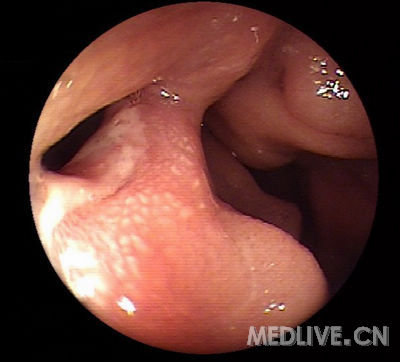

Peutz-Jeghers综合征

Peutz-Jeghers综合征(Peutz-Jeghers’s syndrome,下简称为PJS)又称家族性黏膜皮肤色素沉着胃肠道息肉病,简称黑斑息肉综合征。

本征有3大特征:①黏膜、皮肤特定部位色素斑;②胃肠道多发性息肉;③遗传性。以往认为本病罕见,近年来临床报道病例较多。本病可发生于任何年龄,多见于儿童和青少年,男女发病率大致相同。

Peutz-Jeghers综合征是少见的常染色体显性遗传性疾病,STK11是PJS的易感基因。

PJS主要表现为胃肠道多发性息肉,可见于从胃到直肠的任何部位,尤其好发于小肠,同时有皮肤、粘膜色素沉着,体检时可见到特征性的皮肤或粘膜黑斑,常分布于唇部、口腔粘膜、手指或脚趾、手掌或足底。

内镜下可见散在、多发息肉,常较大并分叶,多有蒂。病理为错构瘤性息肉,其中有平滑肌成分从粘膜肌层如树枝状分枝长入息肉内。

发生胃肠道及卵巢、乳腺、胰腺等部位恶性肿瘤的危险增大,除进行内镜随诊外,尚需注意相应的其他检查。